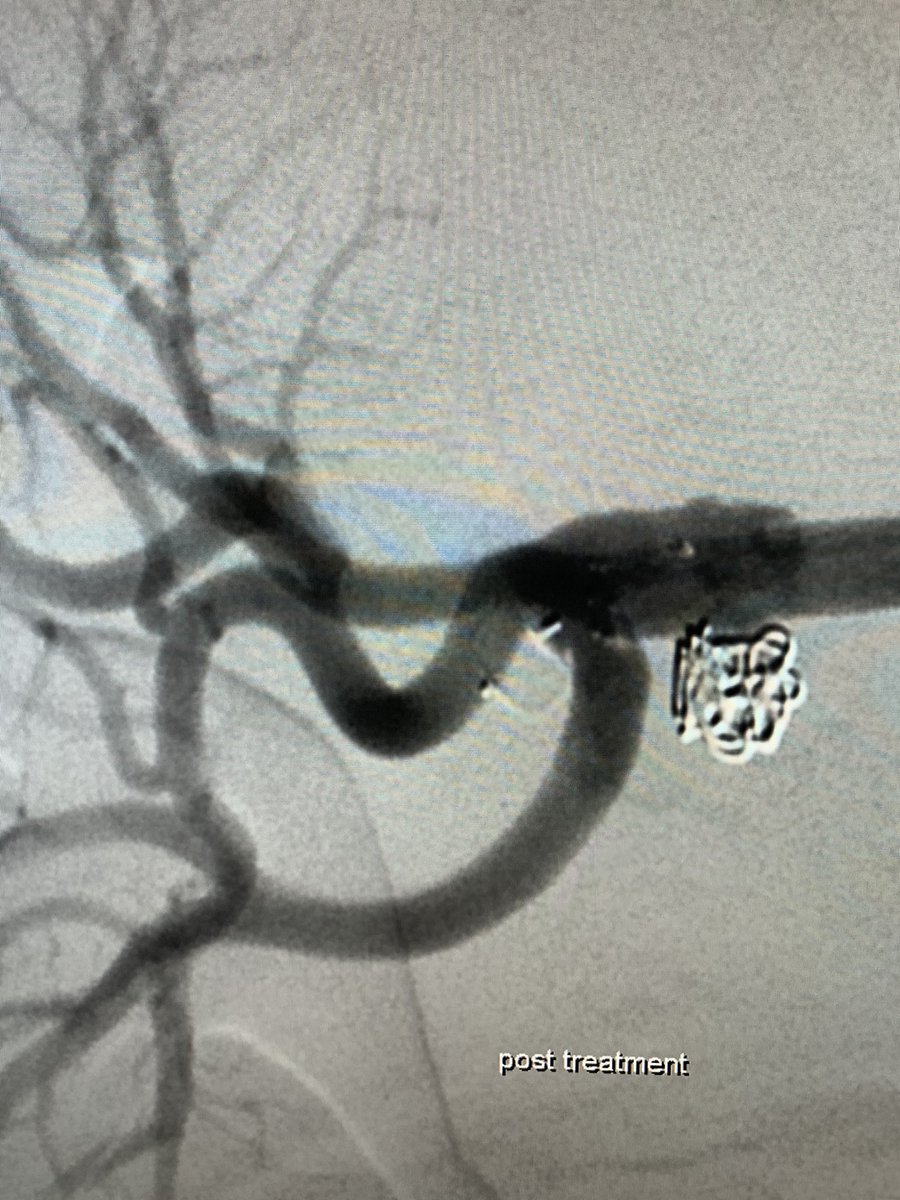

WEB can be used in various anatomical locations. We treated a wide-necked renal artery aneurysm with a WEB by ”corking” the neck. Immediate contrast stagnation!